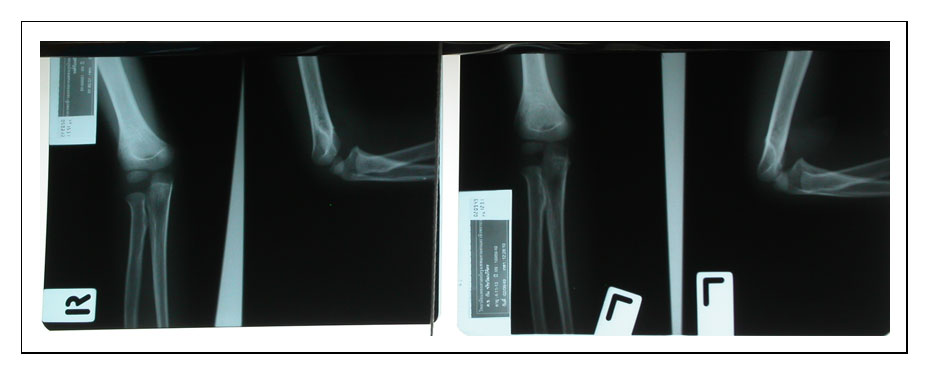

แปลก !!! แพทย์และหมอฮือฮา....เพราะเอกซเรย์พระคุณเจ้ารูปหนึ่งปรากฎว่ากระดูกแขนเป็นแก้วสีใสหมดทั้งตัว พอ สอบถามที่มาที่ไปปรากฎว่าเป็นหลวงพ่อประสิทธิ์ ปุญมากโร แห่งวัดป่าหมู่ใหม่(อ.แม่แตงจ.เชียงใหม่) ท่านก็เป็นพระป่ากรรมฐานศิษย์สายหลวงปู่มั่น ภูริทัตโต คุณหมอทั้งหลายที่ใน ร.พสวนดอก(เชียงใหม่) ต่างยกย่องกล่าวขานถึงหลวงพ่อว่าน่าอัศจรรย์แท้ เพราะเขาถ่าย x-ray ท่านออกมาปรากฎว่ากระดูกข้างในเป็นแก้วทั้งหมด หมอๆ ทั้งหลายในโรงพยาบาลสวนดอก เลยเคารพท่านมาก

- ฟิล์มเอ็กเรย์กระดูกท่านครับ